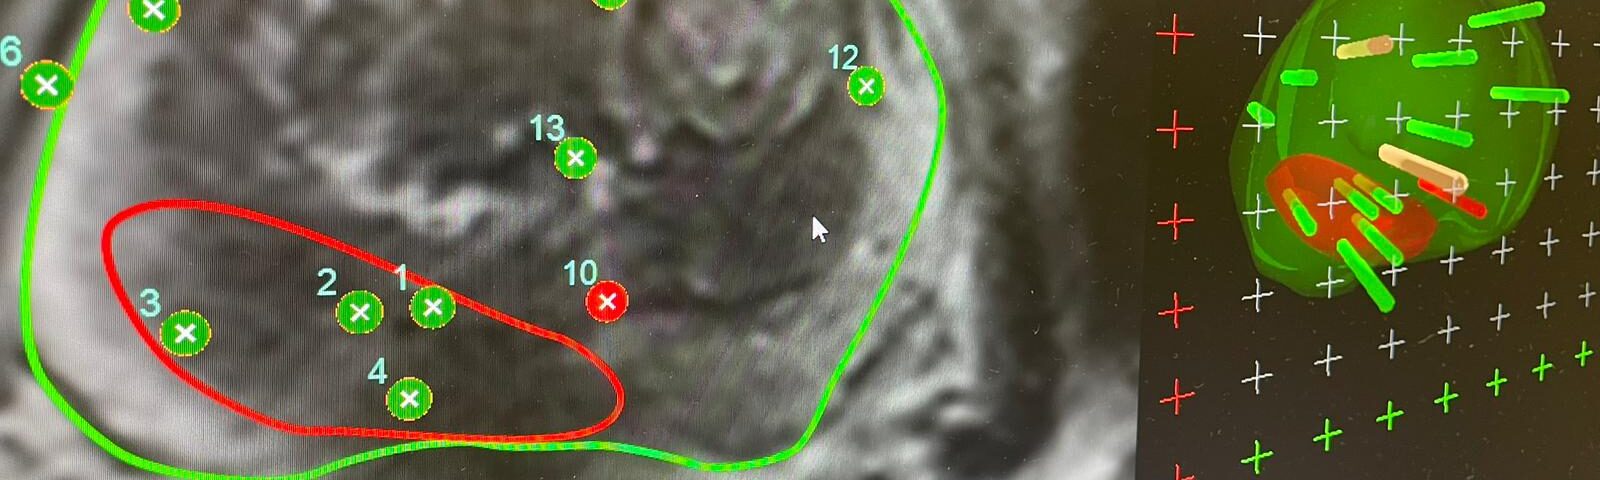

Prostatakrebs zählt zu den häufigsten Krebserkrankungen des Mannes. Standardtherapien wie Operation oder Radiotherapie können den Tumor zwar beseitigen, führen aber nicht selten zu Miktionsbeschwerden oder Erektionsstörungen. Die sogenannte „Fokale Therapie“ verfolgt einen anderen Ansatz: Sie zerstört nur den erkrankten Bereich und belässt den Rest der Prostata unversehrt. Bei der Hochintensitäts-Fokussierten Ultraschalltherapie (HIFU) wird der Tumor mithilfe von Magnetresonanztomografie und Echtzeit-Ultraschall millimetergenau erhitzt und zerstört. Bislang gilt diese Methode laut den Leitlinien der European Association of Urology als experimentell – unter anderem, weil aussagekräftige prospektive Daten fehlten. Die aktuelle Studie der KL Krems und klinischen Partnern in St. Pölten, Baden und Korneuburg liefert die notwendige Evidenz zu diesen Themen.

„Anstatt die gesamte Drüse zu entfernen oder zu bestrahlen, behandeln wir nur den erkrankten Teil – gesteuert durch MRT und Echtzeit-Ultraschall“, erklären OA Dr. Gábor Rosta und Prim. Prof. Dr. Harun Fajkovic von der Klinischen Abteilung für Urologie und Andrologie am Universitätsklinikum St. Pölten, einem Lehr- und Forschungsstandort der KL Krems. „Unsere Ergebnisse zeigen, dass dieser fokussierte Ansatz bei ausgewählten Patienten den Krebs wirkungsvoll kontrollieren und die Nebenwirkungen herkömmlicher Behandlungen signifikant senken kann.“

Im Rahmen der prospektiven Machbarkeitsstudie wurden zwischen 2021 und 2024 insgesamt 51 Männer mit neu diagnostiziertem, lokal begrenztem Prostatakarzinom niedrigen oder mittleren Risikos behandelt (Tumormarker PSA ≤ 15 ng/mL, Stadium ≤ T2). Bei allen wurde die erkrankte Region gezielt mittels MRT-gestütztem HIFU abgetragen. Die Studienteilnehmer wurden über zwei Jahre nachbeobachtet – mit vierteljährlichen PSA-Kontrollen, MRT-Untersuchungen nach 12 und 24 Monaten sowie anschließenden Biopsien.